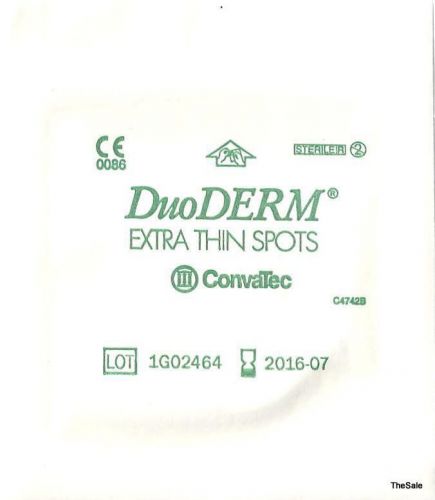

Lot (10) Pieces 1.75x1.5" DuoDerm CGF Extra Thin ConvaTec #187932 Exp 09/2016